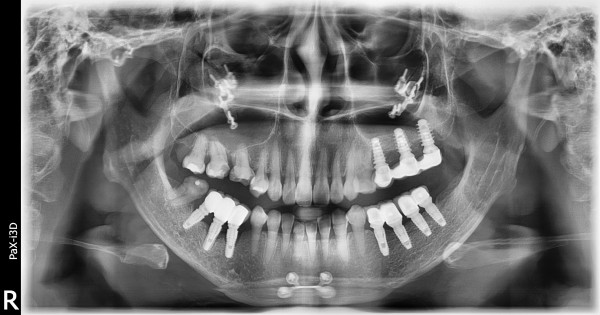

치아교정 | 교정 가능여부좀요

답변이 늦어 죄송합니다. 일반진료 원장님과 교정원장님의 협업진료로 교정이 가능하신지 검진해 보셔야 할 것 같습니다. 시간되실 때 전화주시고 내원 부탁드릴께요^^